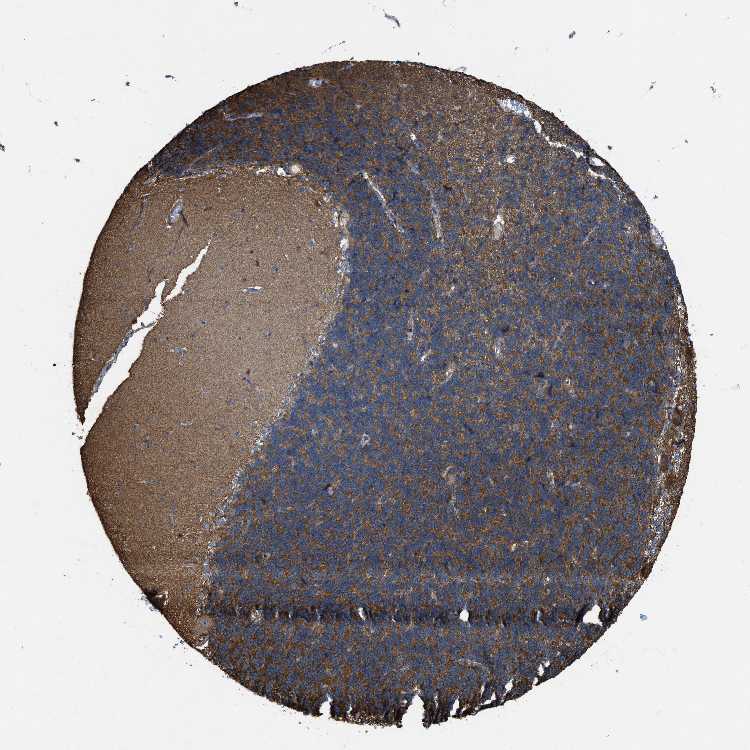

CEREBELLUM - Antibody stainingi

Antibody staining in the annotated cell types in the current human tissue is reported as not detected, low, medium, or high, based on conventional immunohistochemistry profiling in selected tissues. This score is based on the combination of the staining intensity and fraction of stained cells.

Each image is clickable and will lead to virtual microscopy that enables deeper exploration of all samples and also displays staining intensity scores, fraction scores and subcellular localization as well as patient and tissue information for each sample.

Antibody HPA019950

Purkinje cells Low

Cells in granular layer High

Cells in molecular layer Medium